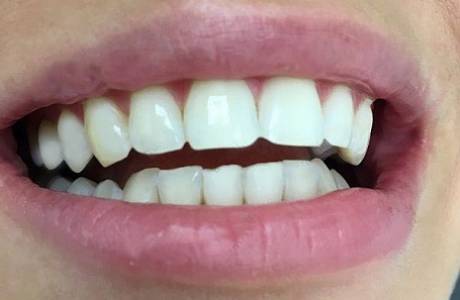

До лечения

Пациент обратился с жалобой на разрушение зубов.

После лечения

На верхней челюсти было принято решение установить E-max коронки.На нижней челюсти E-max виниры. Пациент полностью доволен свой новой красивой улыбкой.